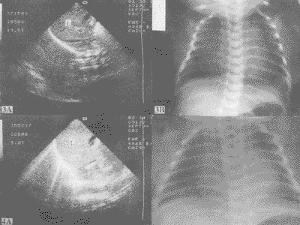

X線表現多樣①肺泡積液征,肺野呈斑片狀,面紗或去霧密度增深影,或呈小結節狀,直徑2~4mm,②間質積液,X線呈網狀條紋影。③葉間胸膜(多在右肺上、中葉間)和胸膜腔積液,量少。④其他徵象,肺門血管瘀血擴張,呈肺紋理影增粗,且邊緣清楚,自肺門呈放射狀向外周伸展。⑤肺氣腫征,透光度增加。X線表現24小時吸收占71%,72小時吸收占97.8%,偶有延長至4天后吸收者。